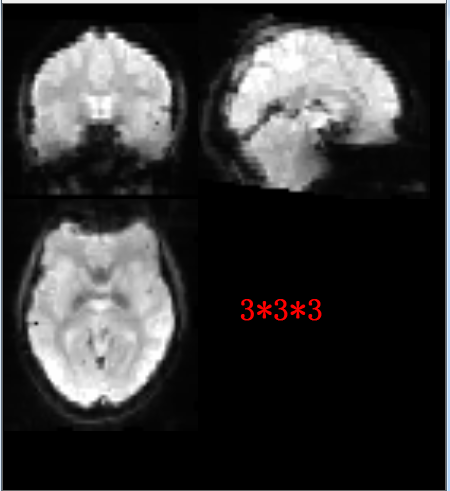

Here are two normalized results for  one identical participate

A short answer is 2*2*2 is not suitable for your data if using DARTEL, as your original resolution should be more than 3.

Our original resolution(slice thickness) is 3.5*3.5*3.5 mm

Since i have checked the template in“DPABI_V3.1_180801\Templates\SPMTemplates\toolbox\OldSeg” size is 2*2*2,so it seems that we need not replace it,and reasonablely we cannot set voxel size 3*3*3 with this original template,am i right?

i.e., with voxel size 2*2*2 and normalize by using T1 image unifiedsegmentation and with voxel size 3*3*3 and normalize by DARTEL

Actually, if the original voxel size is 3.5*3.5*3.5 mm, there is no need to resample to 2*2*2 -- no more information added beyond consuming disk space.

222.png 159.14 KB

333.png 140.75 KB